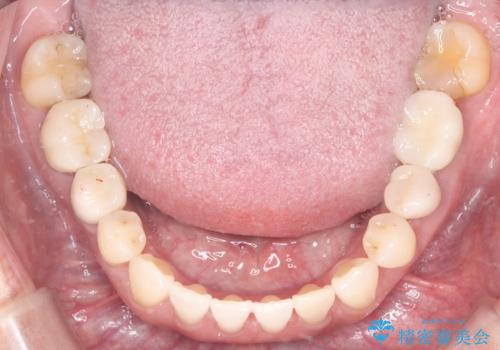

矯正によって土台となる歯列が整った段階で、欠損部位へインプラントを埋入しました。これにより、周囲の歯を削ることなく、天然歯のような噛み心地を再現することができました。

矯正とインプラントを組み合わせたことで、見た目のコンプレックスが解消されただけでなく、全体の噛み合わせも安定しました。隙間がなくなったことで発音や清掃性も向上し、長期的に健康を維持できる口腔環境が整いました。